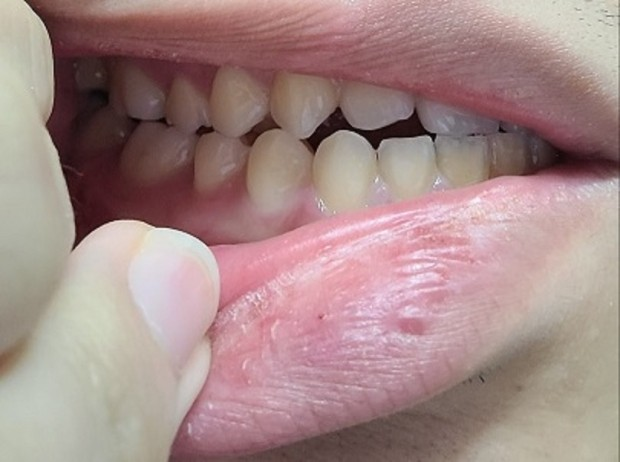

• 1번 째 사진

안녕하세요. 구강악안면외과랑 교정과 돌아봤는데 절단교합인 3급 부정교합이 있고 어금니가 잘 맞지 않는 상태라면서 돌출입 경향에 거미스마일이 있다는 진단과 함께 미세한 비대칭(3mm정도 가량)과 턱끝이 7~8mm(이마뼈 기준 턱 끝이 5mm들어간 위치를 정상으로 볼 때)가량 나왔다는 진단을 받았습니다. 그러면서 발치가 동반되는 돌출입 교정을 하면 주걱턱스러운 부분이 어느정도 개선되지만 중안면부 함몰 및 주걱턱에서 나타나는 중안모가 꺼져서 나타나는 특유의 이상한 느낌에 대한 개선과 하악이 전돌된 부분에 대한 제대로 된 개선​은 어렵다고 했습니다. 그 외의 방법으로의 주걱턱 교정은 외모 개선의 효과는 전혀 없고 교합만 맞춰진다고 했습니다. 그러면서 확실한 외모 개선(중안면부 함몰에 대한 개선과 하악이 전돌된 부분에 대한 개선)을 원한다면 상악의 발치교정으로 위턱이 들어간 상태에서 위턱을 전체적으로 전방이동하는 수술방식 혹은 양악 회전술(전문 용어로 clockwise rotation of maxilla mandibular complex, 이 술식의 경우 하악이 너무 뒤로 이동할 가능성이 높은 술식)과 더불어 이부성형술을 교합만 맞추거나 돌출입만 들어가는 정도로 생각한다면 교정을 생각해보라는 이야기를 들었습니다. 저는 확실한 외모 개선(중안면부 함몰에 대한 개선과 하악이 전돌된 부분에 대한 개선​)을 원하지만 양악수술은 구강악안면외과의 수술 중 비교적 큰 수술에 속하는 만큼 신중히 결정하고자 합니다. 우선 안모, 교합, x-ray 사진자료를 올릴 테니 수술 케이스, 보더라인, 수술 정말 필요없는 케이스 중 어디에 속하는지 대략적인 판단을 부탁드립니다. 선생님 다시 한 번 말씀드리지만 저는 확실한 외모 개선(특히 중안면부 함몰에 대한 개선​)을 원합니다!!!